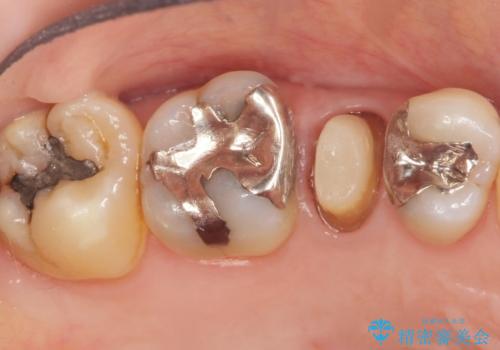

- 歯が欠けてしまったことを主訴に来院された患者様です。

欠けている奥歯(左上5)は失活歯で、保険内の銀の詰め物(メタルアンレー)で治療されていました。

金属の詰め物と土台を除去し、ファイバーコア(金属を使わない強くてしなやかな土台)を植立したのちセラミッククラウンによる補綴治療を行いました。

精査したところ、右上の奥歯(右上5)に根尖病変を認めたため、こちらは根管治療後にセラミッククラウンによる補綴を行いました。